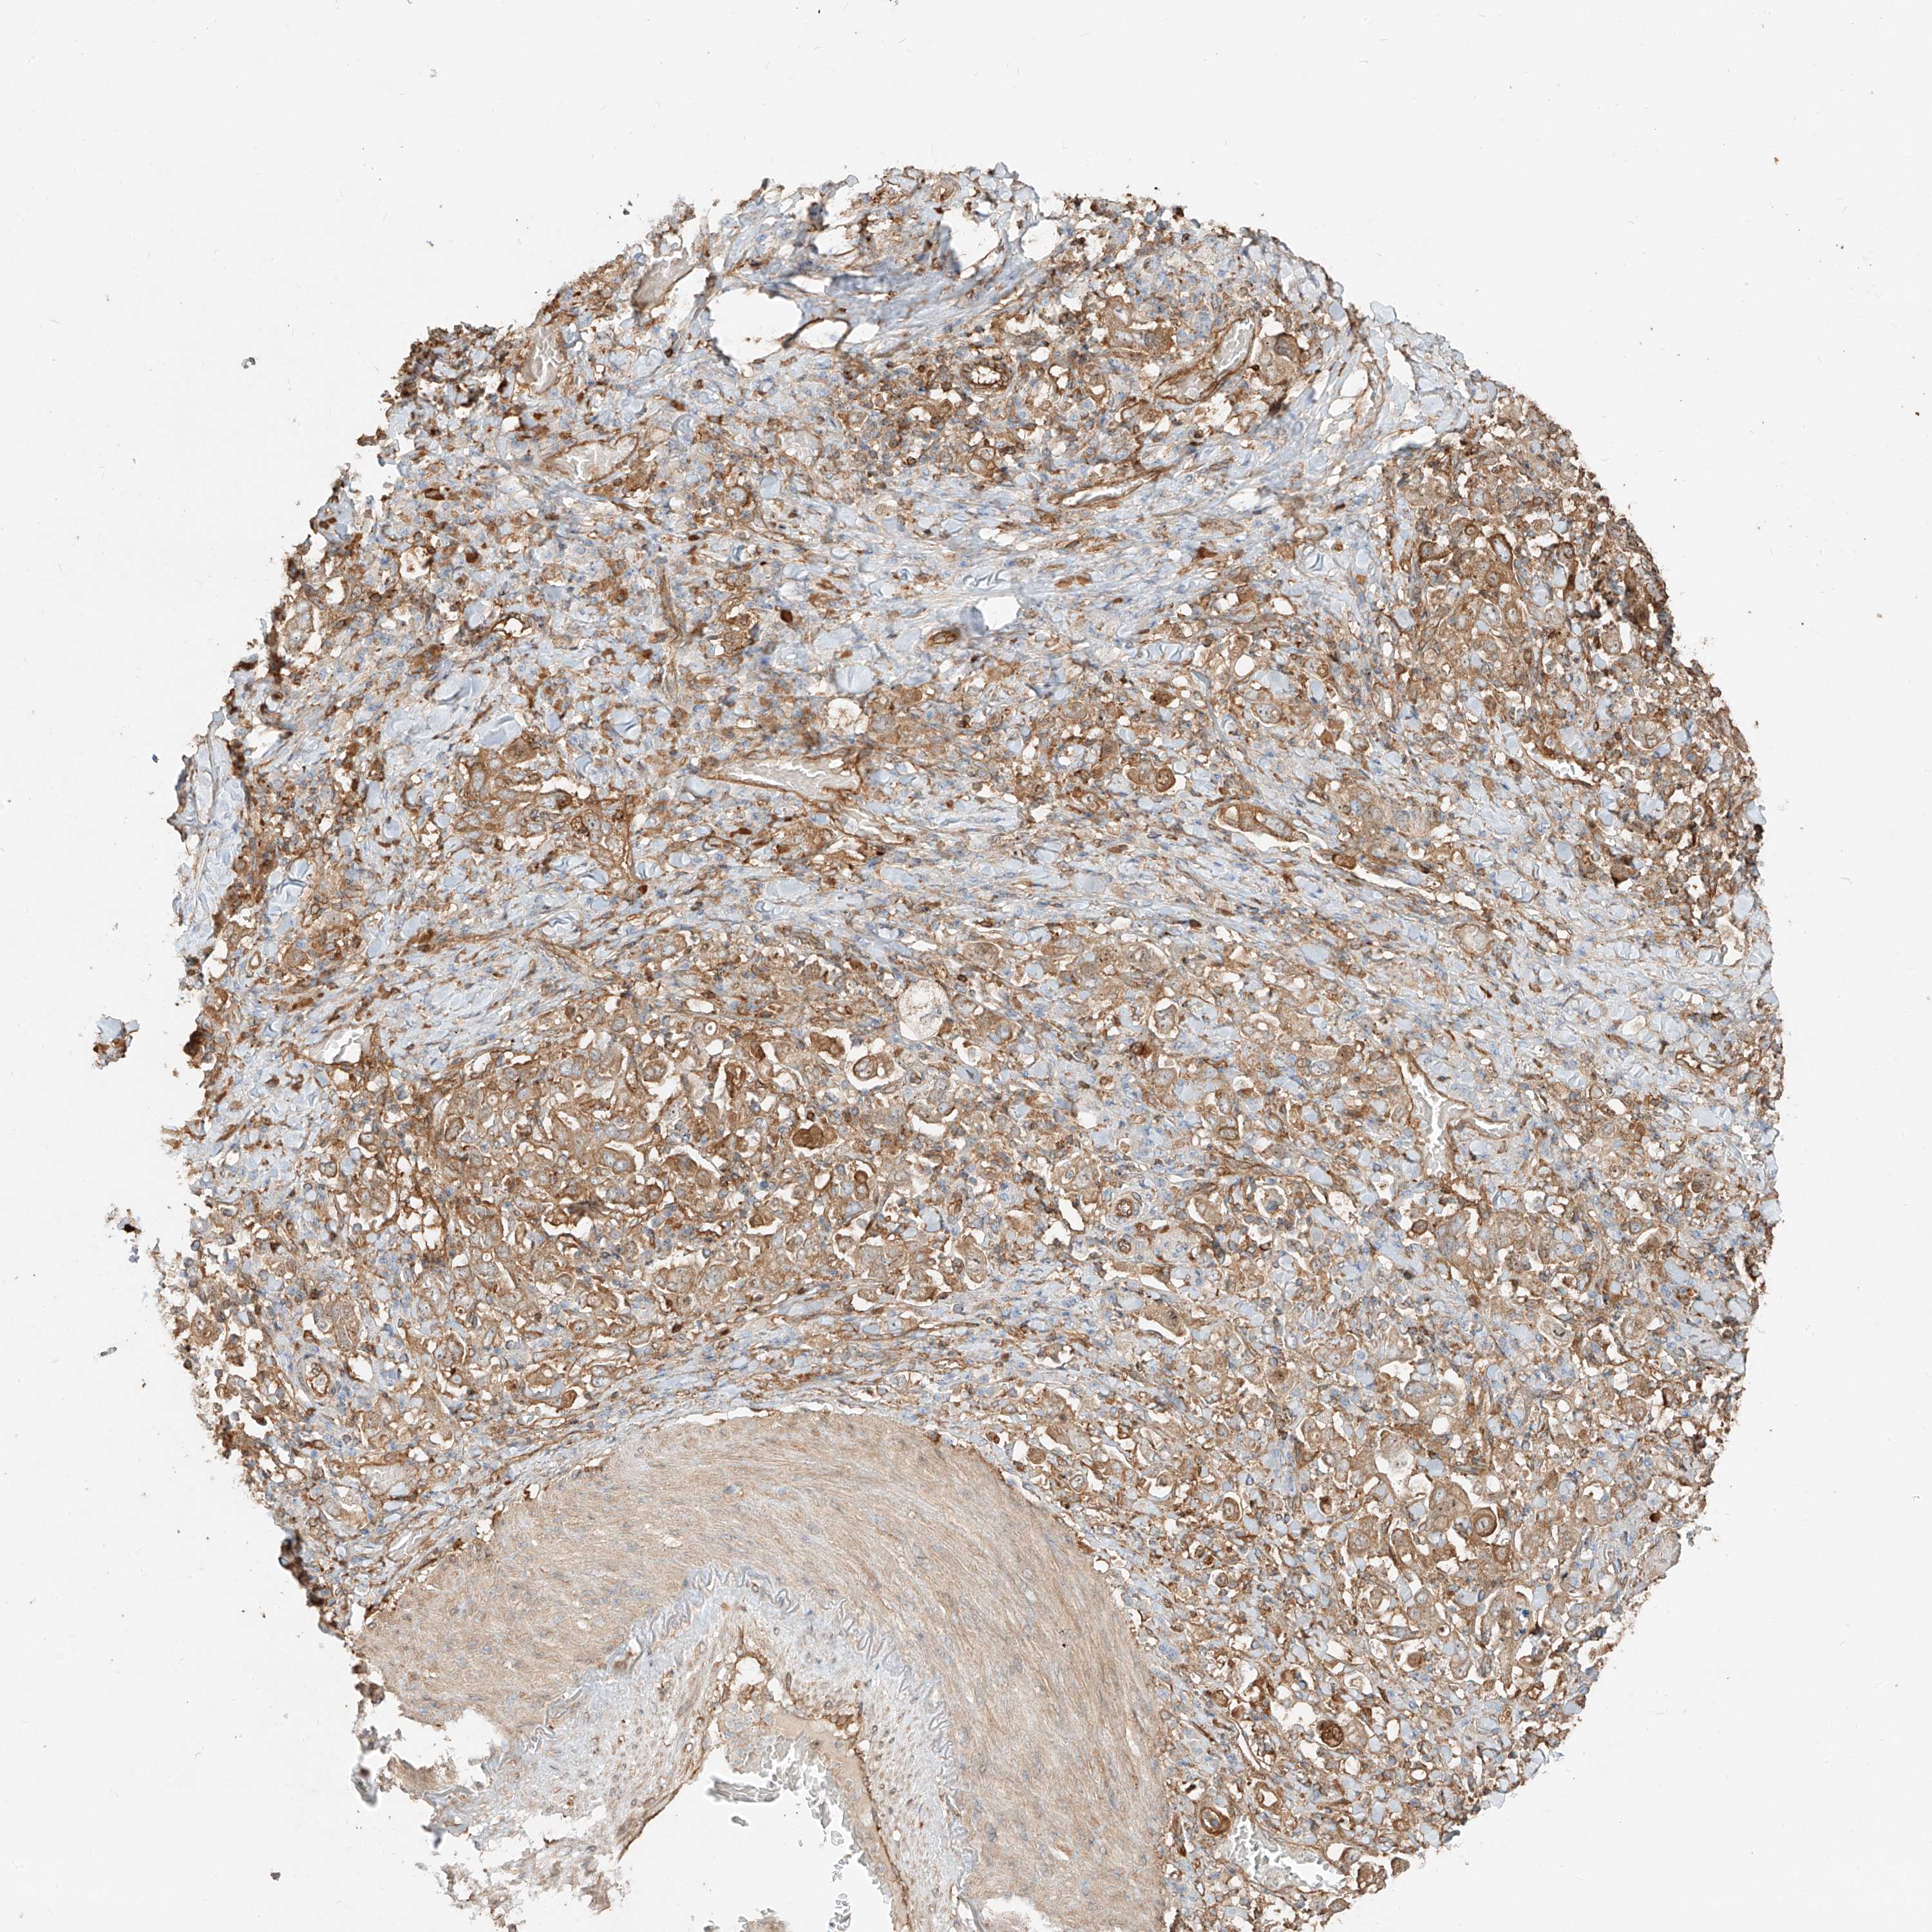

STOMACH CANCER - Protein expressioni

A mouse-over function shows sample information and annotation data. Click on an image to view it in a full screen mode. Samples can be filtered based on level of antibody staining by selecting one or several of the following categories: high, medium, low and not detected. The assay and annotation is described here.

Note that samples used for immunohistochemistry by the Human Protein Atlas do not correspond to samples in the TCGA dataset.

Antibody stainingi

Antibody staining in the annotated cell types in the current human tissue is reported as not detected, low, medium, or high, based on conventional immunohistochemistry profiling in selected tissues. This score is based on the combination of the staining intensity and fraction of stained cells.

Each image is clickable and will lead to virtual microscopy that enables deeper exploration of all samples and also displays staining intensity scores, fraction scores and subcellular localization as well as patient and tissue information for each sample.

Antibody HPA031410

Staining

High

Medium

Low

Not detected

Intensity

Strong

Moderate

Weak

Negative

Quantity

>75%

75%-25%

<25%

None

Location

Nuclear

Cytoplasmic/membranous

Cytoplasmic/membranous,nuclear

Adenocarcinoma, NOS